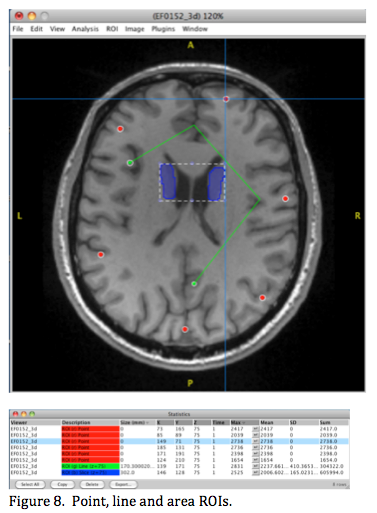

Regions of Interest

Figure 8Mango supports point, line, single-slice (2-D) and multi-slice (3-D) ROIs. A point ROI is indicated in the viewer as a small colored circle (Fig 8, red). When selected for analysis a white ring appears around the circle. A line ROI is defined as a single or multiple line segments of the same color (Fig 8, green). When selected a white ring appears around its end points. A 2-D ROI can be displayed as an outline (edge), filled (mask) or both (Fig 8, blue). When both options are selected the mask transparency defaults to 50%.

To calculate summary stats for an ROI highlight it and select the viewer's menu option Analysis/ROI Statistics. Summary statistics are posted in the 'Statistics' window (Figure 8 bottom). ROI Stats can be calculated for the current slice, all slices, or over the ROIs entire volume (slice range). The large crosshair can be positioned within an ROI by clicking the back-arrow button in its row (Fig 8 bottom). In this example the large crosshair is positioned at the 3rd point ROI.

The statistics table has several options for the size and value headings. In Figure 8 size is in physical units (mm), but it can be toggled to be number of voxels. For point ROIs size is zero (as it should be), length for a line ROI, and volume for 2-D or 3-D ROIs. Even a 2-D or single-slice ROI has units of volume since it has both area and slice thickness. If the area of a 2-D ROI is desired the user can divide the reported volume by the slice spacing. There are several voxel value options, and in Figure 8 it was set to be the maximum value. Other options are minimum value and the value at the ROIs centroid (weighted center of mass). Note: An ROIs centroid may not fall within the ROI, and in Figure 8 it is outside both the line and 2-D ROIs. Also note that the blue ROI in Figure 8 was treated as a single ROI though it consisted of two non-connected components, one in the left hemisphere and one in the right.